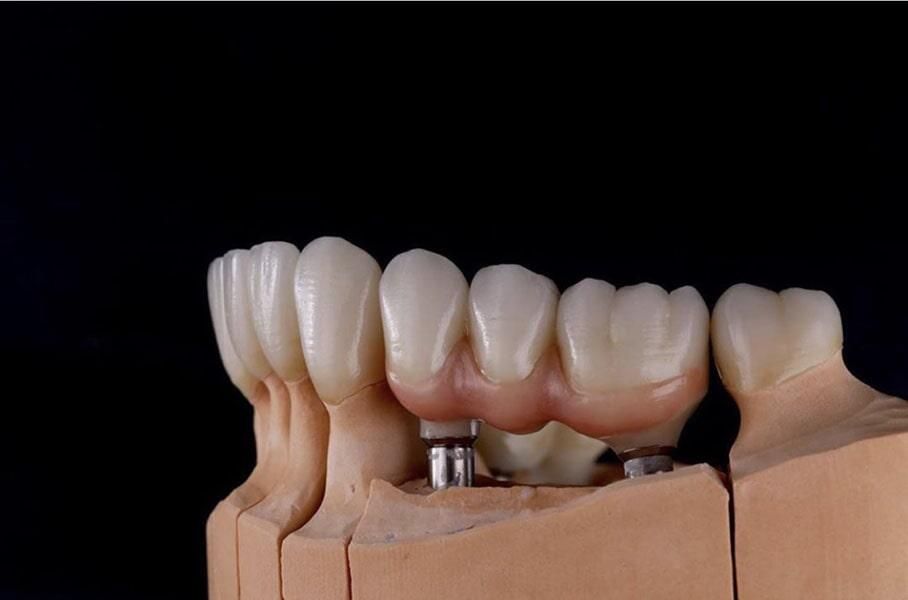

Implantes Dentales

Los implantes dentales son la solución ideal para reemplazar dientes perdidos de manera permanente y segura. Este tratamiento consiste en la colocación de un tornillo de titanio en el hueso maxilar, sobre el cual se fija una corona que imita la apariencia de un diente natural.